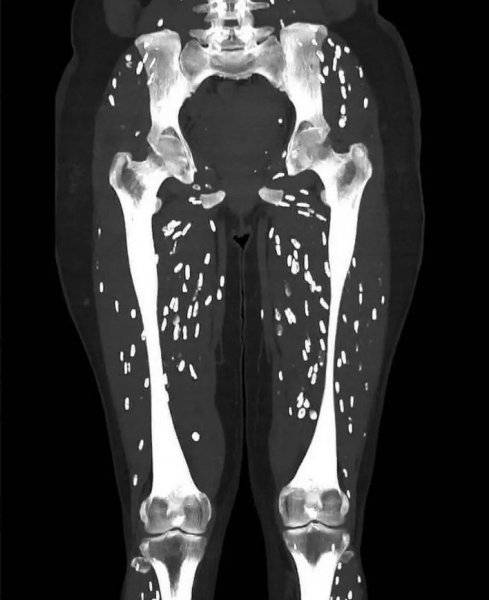

한 대학병원 응급실 의사가 덜 익힌 돼지고기를 먹고 입원한 환자의 매우 심각해 보이는 컴퓨터 단층촬영(CT) 영상을 공유했다.

미국 플로리다 대학병원(UF Health Jacksonville) 응급실 의사인 샘 갈리(Sam Ghali) 박사는 25일(현지시각) 소셜미디어 엑스(X)에 관련 사진을 게재하면서 "내가 본 것 중 가장 끔찍한 CT 영상"이라는 설명을 달았다.

미국 플로리다 대학병원(UF Health Jacksonville) 응급실 의사인 샘 갈리(Sam Ghali) 박사는 25일(현지시각) 소셜미디어 엑스(X)에 관련 사진을 게재하면서 “내가 본 것 중 가장 끔찍한 CT 영상”이라는 설명을 달았다. 환자의 다리 근육 곳곳에 기생충이 박혀 있는 것을 볼 수 있다.

진단명은 낭미충증(cysticercosis). 흔히 ‘돼지고기 촌충’으로 불리는 갈고리 촌충(Taenia solium)의 유충에 의해 감염된다.

관련보도에 따르면 유충은 부화한 후 장의 벽을 뚫고 혈류로 침투하여 인간의 몸 전체로 퍼져 근육이나 뇌에 단단한 석회화한 낭종(물혹)을 형성할 수 있다. 피부 아래에 자리 잡으면 혹처럼 느껴질 수 있다. CT 영상에서 작은 흰색 점들로 보이는 게 바로 이것이다. 갈리 박사는 이를 ‘쌀알 석회화’(rice grain calcifications)라고 표현했다.